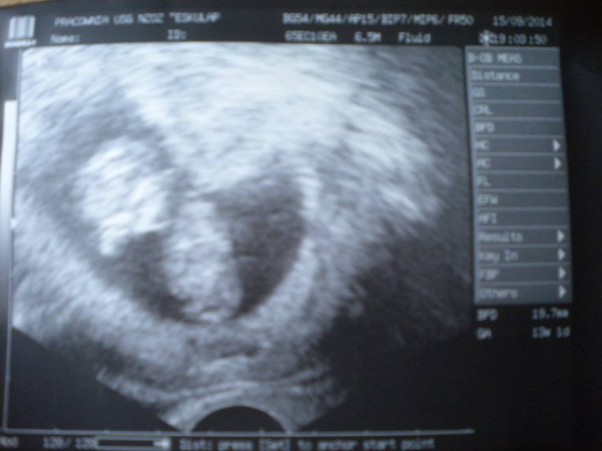

Drugie usg :)